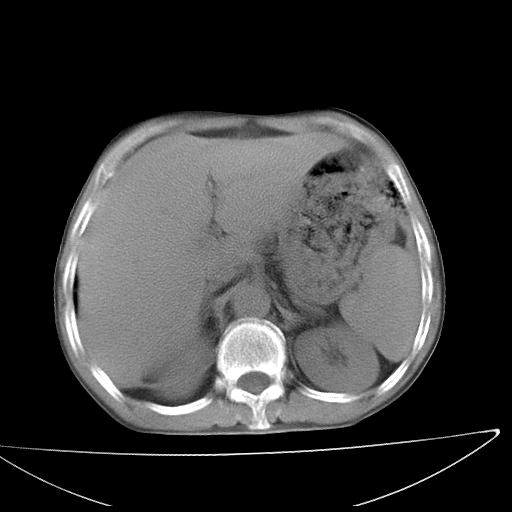

男  70岁,发烧咳嗽4天。盗汗,消瘦。无痰中带血丝,以前有肺tb病史,ct见,双肺tb,左侧胸廓塌陷,左胸膜肥厚粘连。纵隔移位,右侧胸腔积液,大家说说那个心影前左肺舌叶除了肺大炮还有炎症还是干酪性肺炎?有占位吗?我看纵隔淋巴结也大。

1)两肺继发性肺结核并左肺上叶肺不张,支气管扩张。2)双侧胸膜炎(胸膜增厚+少量胸腔积液)。

两肺继发性肺结核并感染,左肺上叶肺不张。建议ct增强。